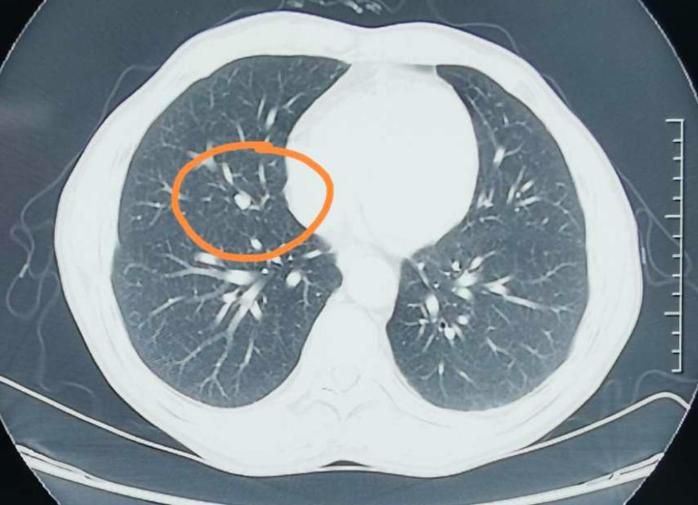

肺部结节是一种常见的肺部疾病 , 其类型多种多样 。 根据结节的大小、形态、密度和生长方式等因素 , 可以将肺部结节分为多种类型 。

1、孤立性肺结节(SPN):这种结节通常只有一个 , 位于肺部的边缘或中心 。 它可能是良性的 , 也可能是恶性的 , 需要通过进一步的检查和诊断来确定 。

2、多发性肺结节:这种结节有多个 , 可以同时出现在一个肺叶或多个肺叶中 。 多发性肺结节可能是良性的 , 也可能是恶性的 , 需要根据具体情况进行诊断和治疗 。

3、磨玻璃结节:这种结节在CT扫描中呈现为磨砂玻璃一样的外观 , 通常是由于肺部炎症、水肿或出血等原因引起的 。 磨玻璃结节可能是良性的 , 也可能是恶性的 , 需要进一步检查以确定性质 。

4、实性结节:这种结节在CT扫描中呈现为高密度的影子 , 通常是由于肺部肿瘤、良性肿瘤或瘢痕等原因引起的 。 实性结节可能是恶性的 , 也可能是良性的 , 需要通过进一步的检查和诊断来确定 。

5、混合性结节:这种结节同时包含磨玻璃和实性成分 , 通常是由于肺部肿瘤和炎症等原因引起的 。 混合性结节可能是恶性的 , 也可能是良性的 , 需要根据具体情况进行诊断和治疗 。